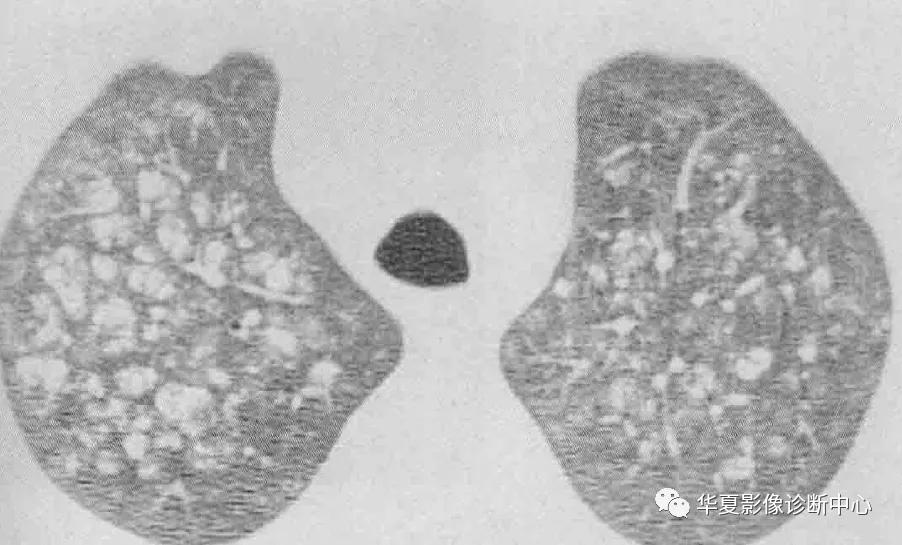

影像学表现:X线特征性表现为爽哦片状实变内隐约可见结节,50%病例实变分布于肺门周围,其余病例随机分布或主要分布于周边或基底部,有时肺实质受累不对称或单侧受累。CT主要典型表现为双侧磨玻璃影(尤其肺背侧部分),几乎均匀累及全非,也可以下肺分布为主,大部分病例可见碎石铺路征,即一个细线形成的直径3-10mm多边形叠加在磨玻璃影上,反应了肺间质水肿的存在或小叶间隔毗邻的空腔内脂蛋白样物质的聚集;正常和异常肺实质边界锐利清楚。